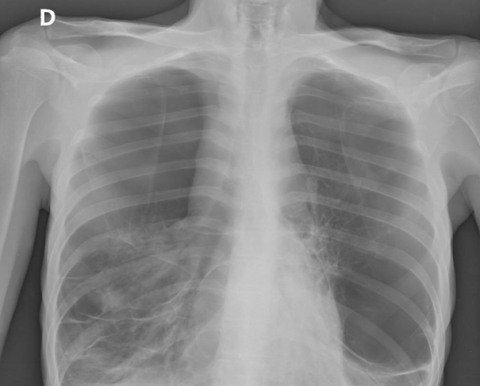

Un homme de 35 ans, ayant comme seul antécédent un tabagisme sévère (notamment cannabinoïde) et vivant dans la rue, est retrouvé par la brigade des sapeurs-pompiers en détresse respiratoire.

Il présente une défaillance respiratoire subfébrile isolée s’étant installée depuis quelques jours. Il nécessite la mise sous oxygénothérapie jusqu’à 10 L/min au masque à haute concentration pour maintenir une saturation à 95%. A l’examen physique, il présente une diminution diffuse et bilatérale du murmure vésiculaire.

Il est amené au service d’accueil des urgences le plus proche où une radiographie thoracique face/profil) est rapidement réalisée.